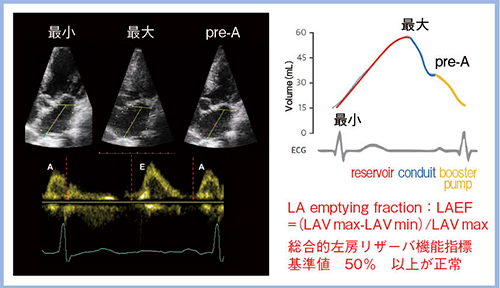

日立の超音波診断装置では,“2D Tissue Tracking”(2DTT)により左房容積の時相変化をダイナミックにトラッキング可能である(図2)。左房は,心電図のQRS波のR波の始点でLAVmin,T波の終わりにLAVmax,U波の前にpre-Aの時相(左房収縮直前)の容積(LAVpre-A)へと変化する。そして,LAVmin,LAVmax,LAVpre-Aの境界時相の容積は,それぞれ左房のreservoir(貯留)機能,conduit(導管)機能,booster pump(後押し)機能を表している(図3)。また,LAVmaxとLAVminから求められるLA emptying fraction(LAEF)は,総合的左房リザーバ機能指標とされており(基準値:LAEF<50%),左房容積とLAEFの組み合わせは,心房細動の出現予測に有用であることが報告されている7)。

図3 左房容積の変化とLAEF